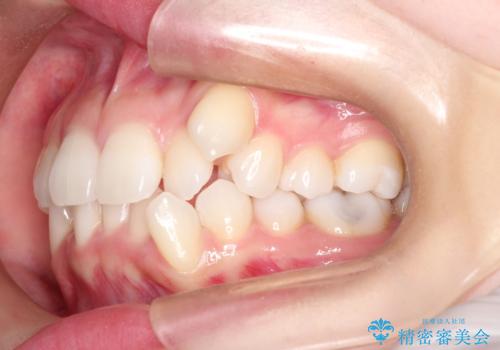

【審美ワイヤー】八重歯を治したい。

- 左上の犬歯の凸凹や正中のずれを主訴に来院されました。

凸凹を治すために、上下左右の小臼歯を抜歯してワイヤー矯正を行いました。